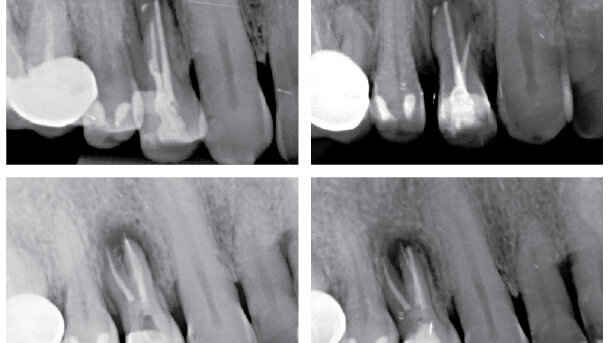

Uzávěr kořenového systému byl proveden dle techniky kontinuální kondenzační vlny s Alpha II a Beta zařízením (B&L Biotech; Obr. 2) a vstup do kořenových kanálků byl uzavřen kompozitem Gradia Flow (GC). Po zaplnění kořenových kanálků byly zhotoveny tři rentgenové snímky: jeden v normální angulaci a dva angulované (obr. 3a – c). Rentgeny jasně ukazují komplexnost kořenového systému a 3D obturace. Zub byl postendodonticky zrekonstruován pomocí Miris 2 (Coltène/Whaledent).

Dvaadvacetiletý pacient byl na naši kliniku odeslán z důvodu bolestivosti zubů 45 a 46. Jednalo se o celkově zdravého pacienta s mírnou až akutní bolestivostí zubů na poklep. Odesílající lékař byl znepokojen celkovou anatomií. Po zhotovení preoperativního rentgenového snímku (Obr. 4) byl proveden trepanační otvor pomocí vrtáčku Crown Cutter a vrtáčku s neaktivní pracovní částí (KOMET/Gebr. Brasseler). Očištění kavity bylo provedeno Start-X-ultrazvukovou koncovkou č. 1 a Muellerovým vrtáčkem č. 3 (Mani, Inc.; obr. 5).

Vstupy do kořenových kanálků byly zkalcifikované, přístup byl získán pomocí nástroje ProTaper SX, pracoval jsem kartáčovitým pohybem. Opracování kanálků bylo provedeno 10.02 K-Flexofilem (DENTSPLY Maillefer) za pomocí Glyde Gel (DENTSPLY Maillefer). Průchodnost byla ověřena PathFily a kanálky byly opracovány za použití ProTaper Systému (DENTSPLY Maillerfer). Po apikálním tvarování byly čtyři kanálky opracovány nástrojem ProTaper F3 s irigací 5% hypochloridem sodným. Finální výplach byl proveden ultrazvukově aktivovaným 5% roztokem hypochloridu sodného, 40% roztokem kyseliny citronové a 95% etanolem. Kořenová výplň byla zhotovena pomocí Alpha II a Beta zařízení za použití techniky kontinuální kondenzační vlny a vstup do kořenových kanálků byl uzavřen kompozitem (Gradia Flow; Obr. 6).

Zub byl postendodonticky zrekonstruován pomocí čepu vyztuženého skelnými vlákny a kompozita (Core-X Flow a Ceram-X Duo, DENTSPLY DeTrey) a byl zhotoven pooperační RTG snímek (Obr. 7)